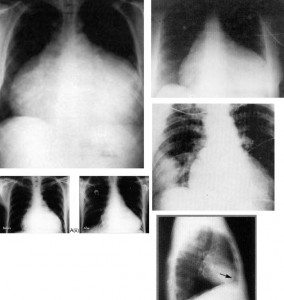

Teleradyografi: Akut perikarditlerde kalp kontürü fazla büyümez. Efüzyonlu perikarditlerde çadır manzarası görülür.

perikarditler-rontgen-2